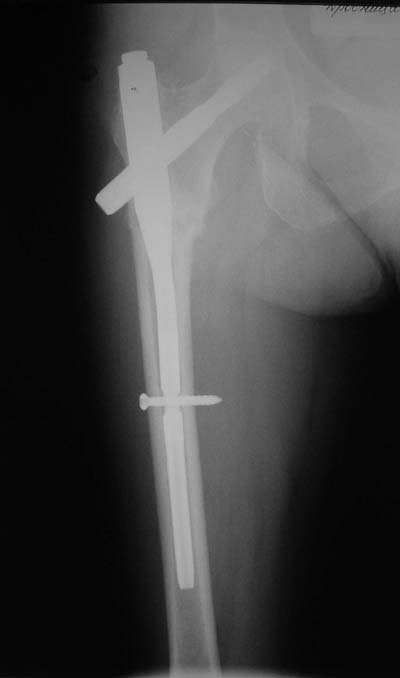

Да? Качество рентгенограмм конечно неочень, но ведь это нестабильный перелом 31.А2.2, не так ли?

Не думаю так. см вложение.

Ну, после помещения туда такого гвоздя даже без дистального винта заметной нестабильности уже не остается ;-)